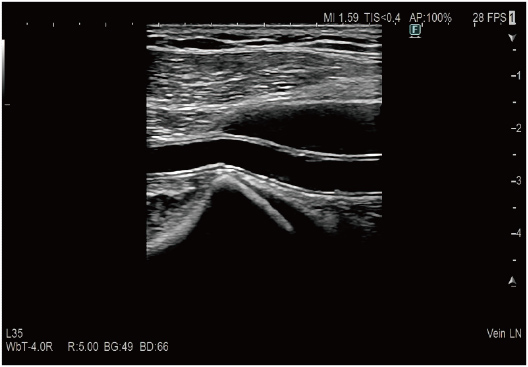

Focused at all depths

Tissue structures such as vessel wall can be delineated clearly keeping the texture and the expression of surrounding tissue. The evolved edge emphasis processing technology can extract the structures effectively.